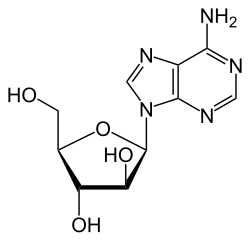

Vidarabine

| Formula | C10H13N5O4 |

| Molar mass | 267.245 g·mol−1 |

Vidarabine or 9-β-D-arabinofuranosyladenine (ara-A) is an antiviral drug which is active against herpes simplex and varicella zoster viruses.

Vidarabine works by interfering with the synthesis of viral DNA.[4] It is a nucleoside analog and therefore has to be phosphorylated to be active. This is a three-step process in which vidarabine is sequentially phosphorylated by kinases to the triphosphate ara-ATP. This is the active form of vidarabine and is both an inhibitor and a substrate of viral DNA polymerase.[5]